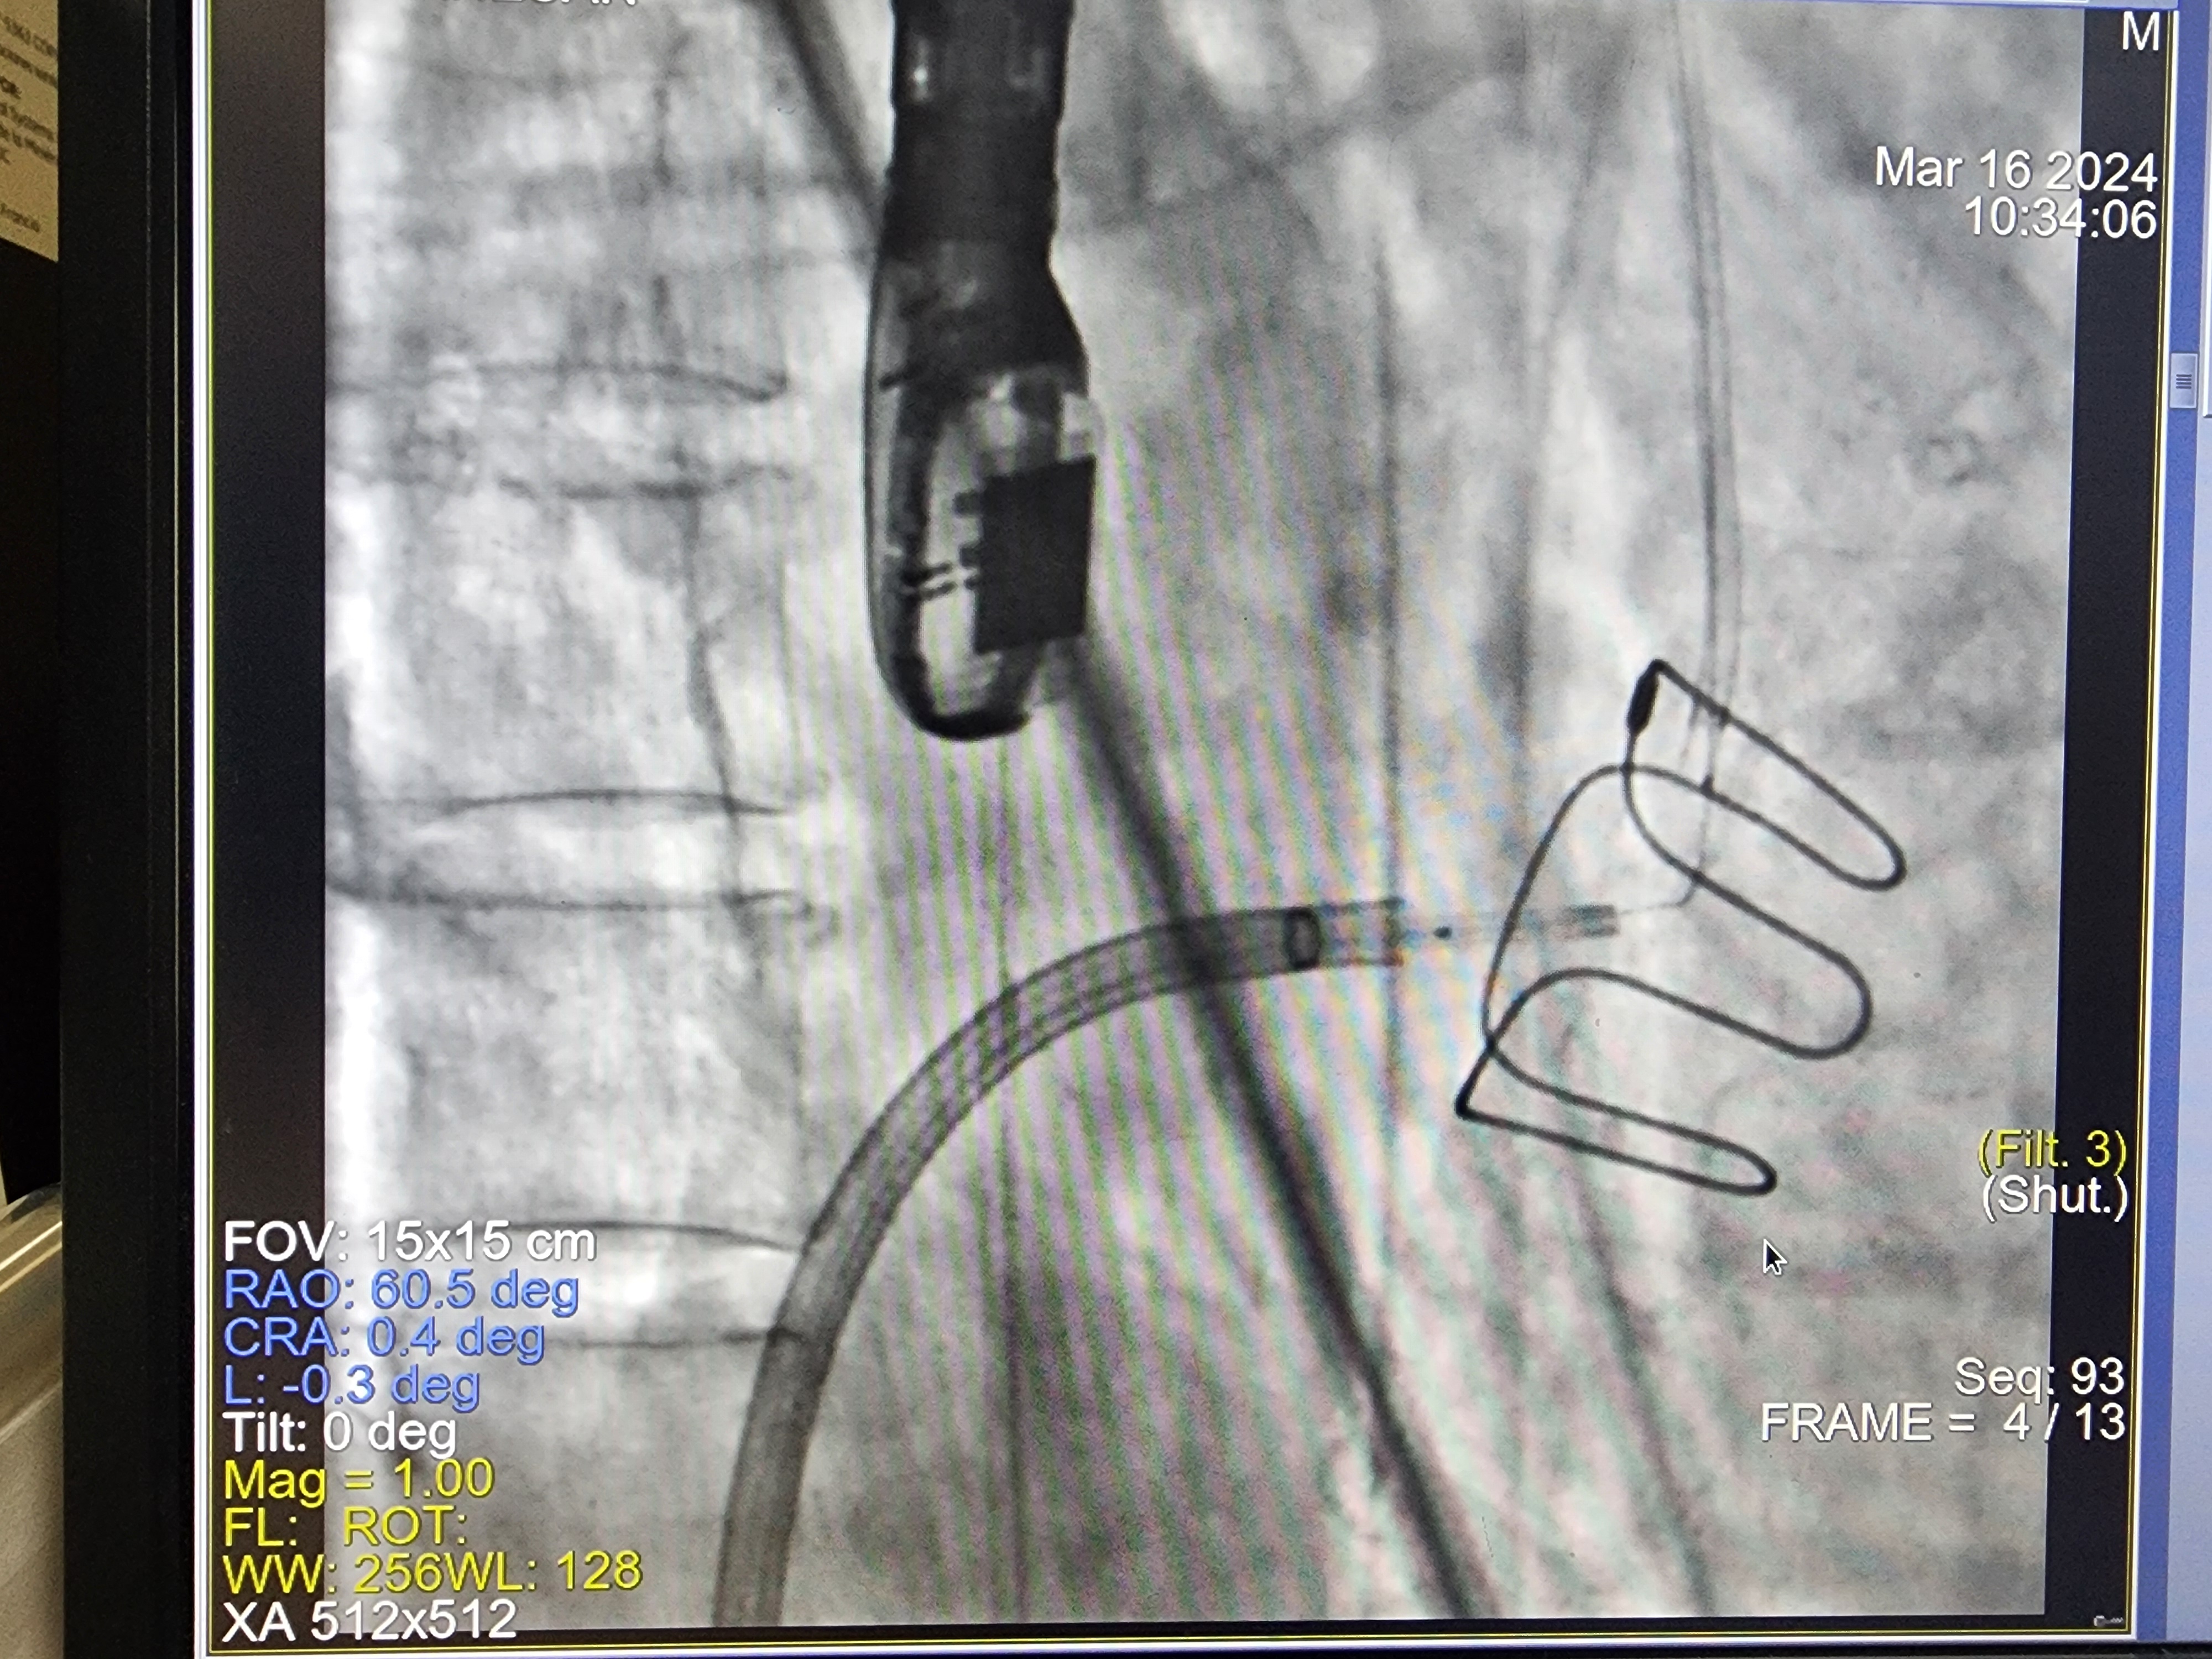

* A 0.014-inch Astato XS20 wire was prepared: its mid-segment was kinked and focally denuded outside to form a 'Flying V'.

Transcatheter Tip to base LAmpoon was completed as per standard technique. TEE confirmed the successful tip-to-base laceration of the mitral leaflet.